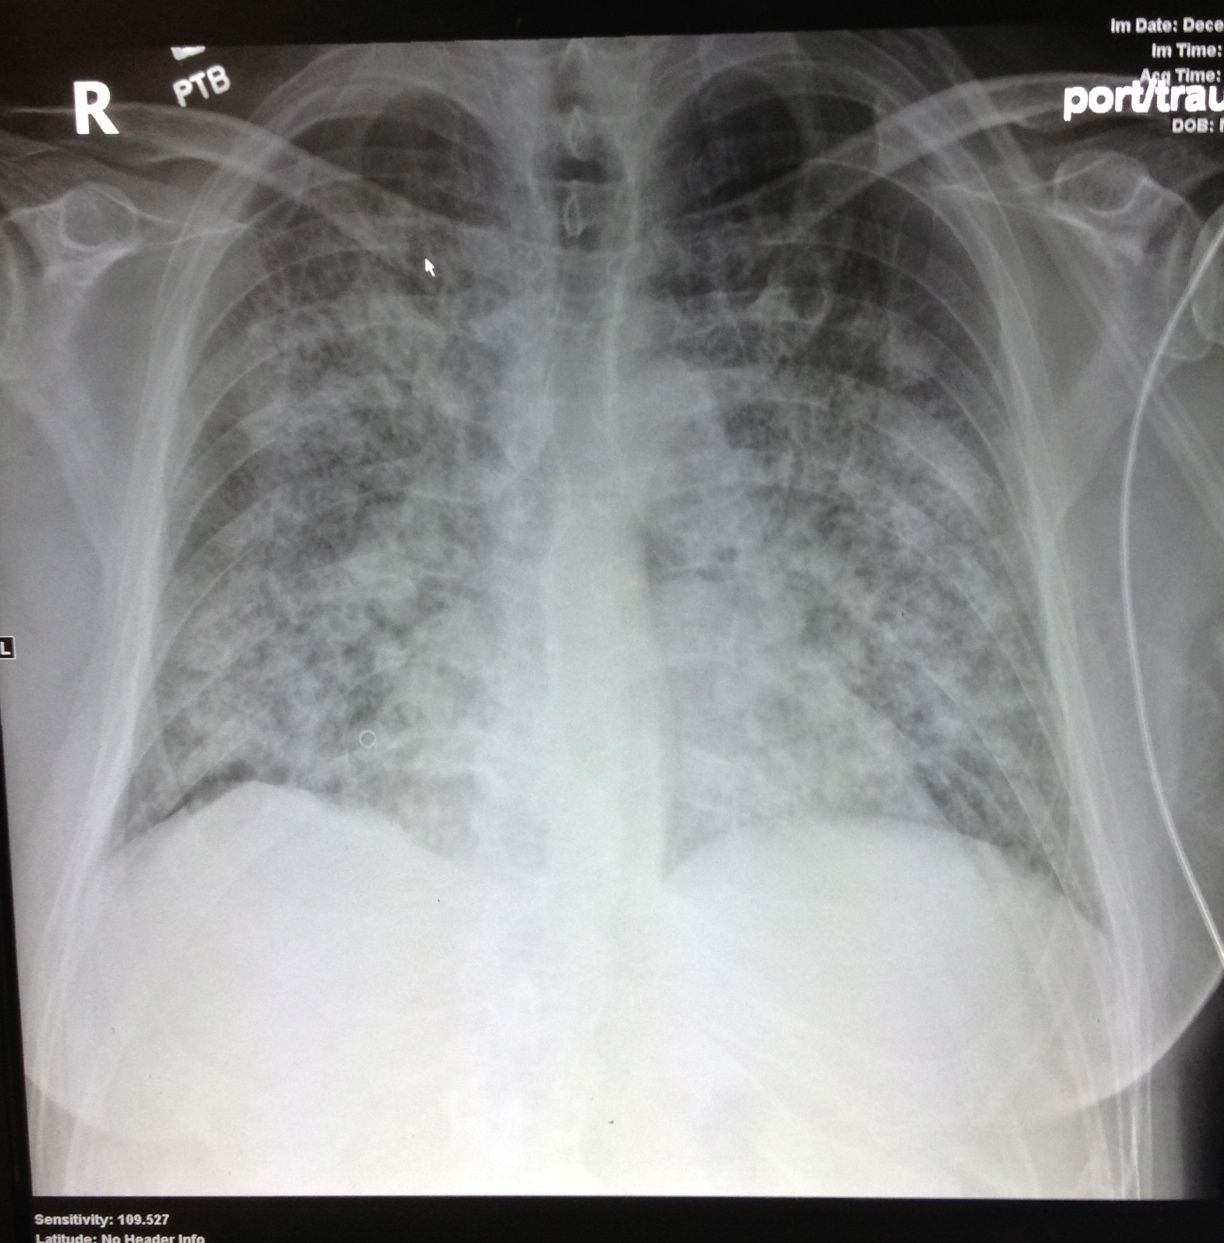

Now back to our patient. She is a 46 year-old female with COPD that had right heart enlargement, which we learned above can be seen in COPD without the presence of a PE. You were unable to get a good subcostal view of the heart to measure the lateral wall, mostly because the patient did not tolerate being laid flat. You move on to the lungs and in the lower right thorax and there you find two hypoechoic, pleural based lesions. Heparin and a CT scan are ordered, and the CT scan shows a large clot located in the right main pulmonary artery.